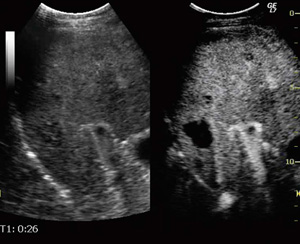

上記のような特性の異なるイメージは,組み合わせて表示することも可能である。Hybrid Contrast表示は,“Hybrid Map”を用いてTissueイメージにContrastイメージを異なる色調で重ね合わせたもので,背景となるTissueイメージ上に造影効果が色調の変化として表現されるため,造影効果の視認性が高まるとともに,対応部位の把握に有用である。Hybrid Angio表示は,ContrastイメージにAngioイメージを異なる色調で重ね合わせたもので,Contrastイメージが示す造影効果のうち,Angioイメージが示す血流像が異なる色調として強調されるため,早期相における血管構築の把握が容易となる(図2)。また,同時2画面表示“DualView”では,画面の右側には選択したイメージが,左側にはTissueイメージが表示される(図3)。これらの各種表示モードは,スキャン中,フリーズ後を問わず,タッチパネル等で容易に切り替えることができる。

図2 末梢型肝内胆管がんの表示モード切り替え例

(画像ご提供:江口病院・小野尚文先生)

図3 Contrast DualView

(画像ご提供:駿河台日大病院 小川眞広先生)